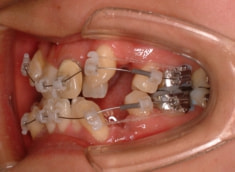

治療開始から約1年後

治療法:表の矯正(T21ブラケット)

ご出産のため治療中断期間あり